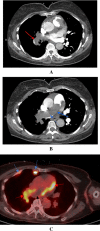

Cases from a busy nuclear cardiology laboratory